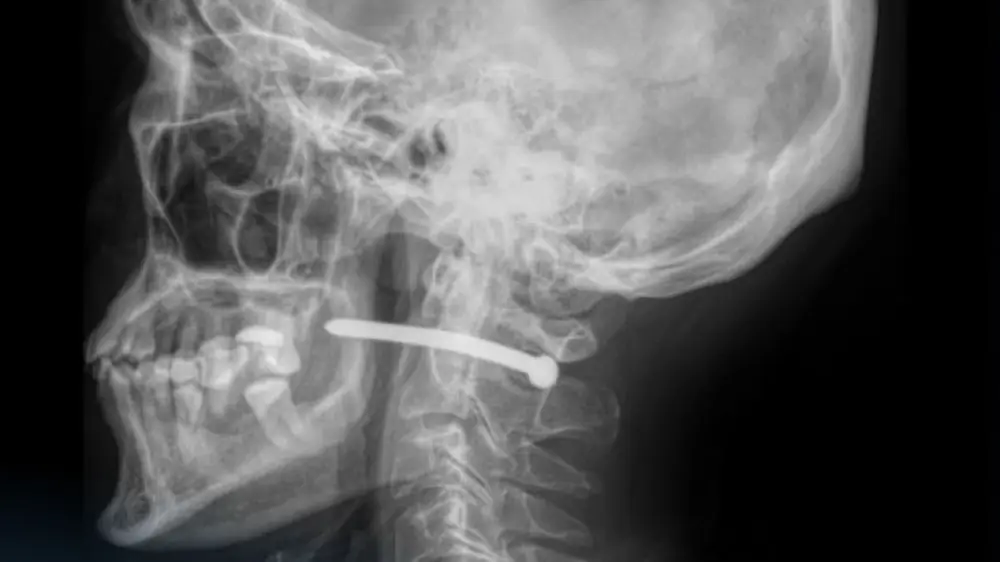

В Петропавловске мужчина едва не погиб во время ремонта: он случайно выстрелил себе в шею гвоздём из пневмопистолета, передаёт корреспондент Tengrinews.kz.

Как рассказали в многопрофильной городской больнице скорой медицинской помощи, 51-летний мужчина обратился с раной в заушной области.

"Как выяснилось, во время ремонтных работ он по неосторожности получил травму гвоздём из пневматического пистолета. Рентген показал, что гвоздь прошёл рядом с шейным отделом позвоночника", - сообщили подробности в пресс-службе медучреждения.

Врачи подчеркивают, что мужчине очень повезло: жизненно важные структуры не были задеты.

"Травмы в области шеи крайне опасны, ведь рядом проходят крупные сосуды, нервы, дыхательные пути и спинной мозг. Даже небольшое повреждение может привести к серьёзным последствиям", - отметили в медучреждении.

Челюстно-лицевые хирурги больницы удалили инородное тело, провели ревизию и обработку раны, а также наложили швы и стерильную повязку.